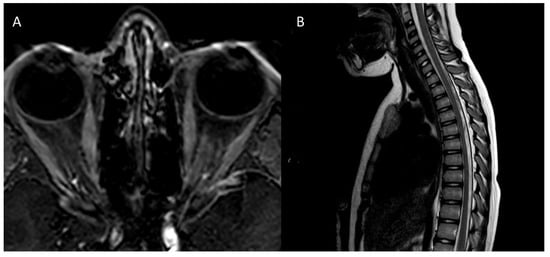

| MRI | Left optic nerve: hyperintensity (T2) Two millimetric T2 hyperintense cerebellar foci | Right optic nerve: hyperintensity (STIR), contrast enhancement ADEM outcomes | Right optic nerve: small hyperintensity (T2) Multiple juxtacortical, infratentorial, and periventricular demyelinating lesions; four lesions with contrast enhancement | Right and left optic nerves: retrobulbar bilateral swelling, contrast enhancement |